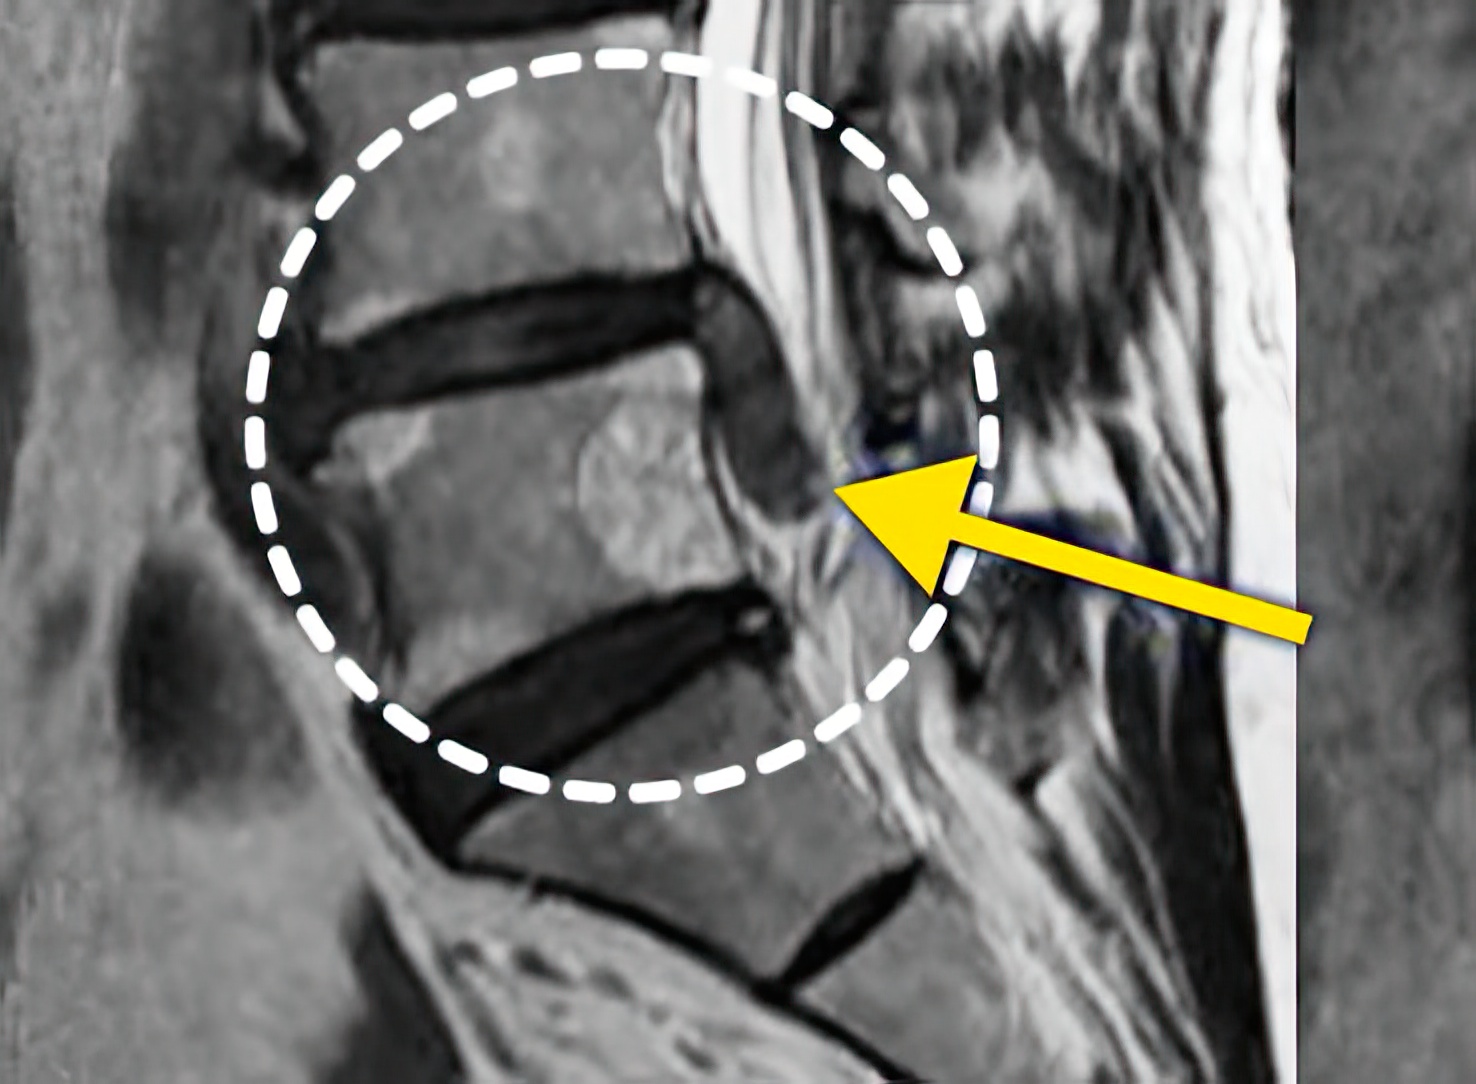

자생 비수술 한방통합치료 후

터진디스크가 흡수된 모습

Before

터진디스크 한방통합치료 전

After

터진디스크 한방통합치료 후

비수술 치료만으로

터진 디스크 흡수

튀어나온 디스크 대비,

터진 디스크 치료 효과 우수

디스크 흘러내린 정도가

심할수록 흡수 가능성 증가